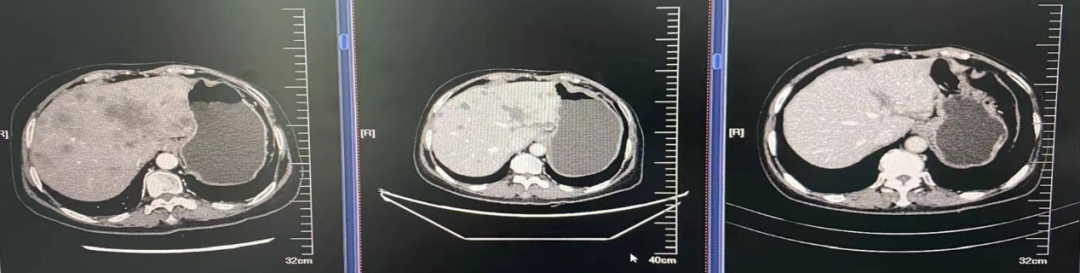

图5.肝脏穿刺病理及免疫组化

2021年4月9日肝脏穿刺病理及免疫组化:ACK7(+)、CK19(+)、GATA-3(弱+)、SOX-11(-)、GCDFP-15(+)、Mammaglobin(弱+)、AFP(-)、Hepatocyte(-)、Arg(-)、CK5/6(-)、ER(<1%)、PR(-)、CerbB2(3+)、Ki-67(+15%)